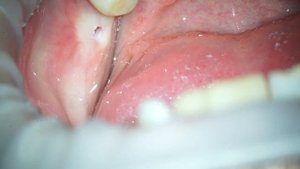

Сложные операции по урологии в ПКМЦ. Лазерное лечение камней мочеточника. Удаление аденомы простаты.